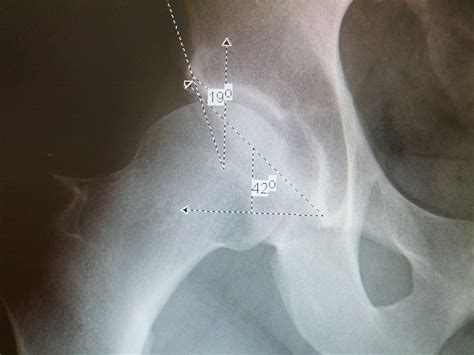

Diagnosing a labral tear involves a combination of physical examination and imaging tests. A healthcare provider will typically perform the following steps:

• Imaging tests, such as X-rays, MRI, or CT scans

Imaging tests are particularly important for confirming the diagnosis and determining the extent of the tear. An MRI is often the preferred method due to its ability to provide detailed images of the soft tissues in the shoulder.